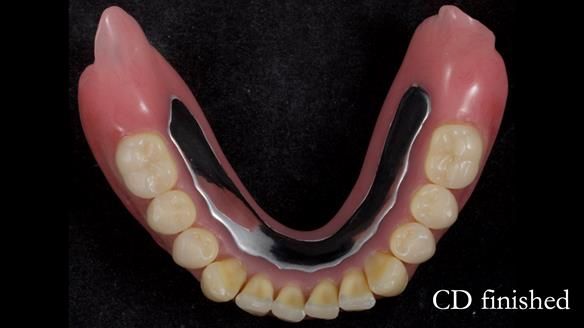

The detailed clinical situation and treatment process are outlined below, with clinical work provided by me and technical work by Rowan Garstang. The treatment spanned 12 months, involving removing 5 upper anterior teeth, adding to an existing upper RPD, followed by creating and fitting metal based complete dentures.